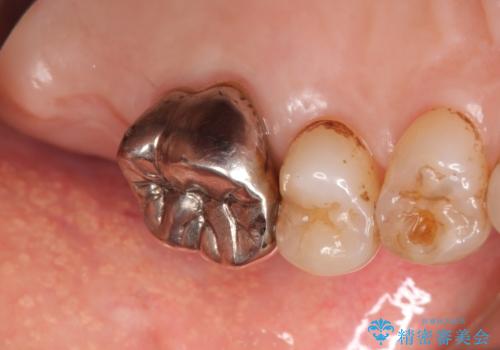

患者様のご希望により抜歯してインプラントによる治療を行いました。

上顎洞が近接しており上顎骨の厚みが薄いことから、ソケットリフト(上顎洞底挙上術)をインプラント埋入と同時に行いました。